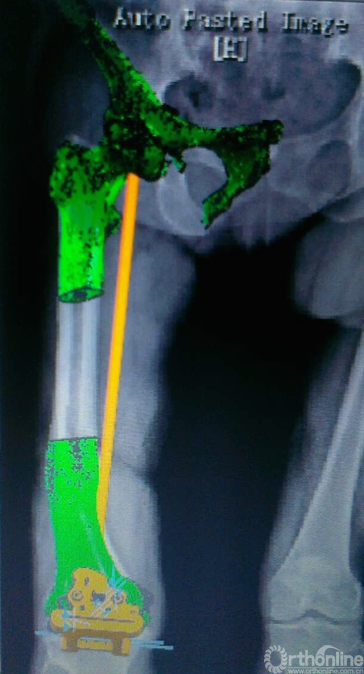

(3)右下肢全长CT扫描,将DICOM格式文件输入Materialise Mimics17.0中,进行三维重建,确定股骨头旋转中心,膝关节中心及踝关节中心,标记股骨、胫骨机械轴,冠状位垂直于机械轴确定股骨、胫骨截骨方向,并以初次置换标准确定截骨厚度(图2a,2b);

(4)选取手术中可以确定显露的骨性结构表面,逆向求得反向模型。设计生成导板STL文件,在EOS FORMIGA110设备中使用医用塑料PA2200进行3D打印,制作截骨导板,消毒后备用(图3a,3b)。

图2a. 右下肢CT扫描,三维重建后,和右下肢全长叠加,在软件中确定股骨机械轴,并设计截骨导板。

图2b. 确定截骨的厚度。

图3a.股骨远端模型及股骨侧截骨导板。

图3b. 胫骨近端模型及胫骨侧截骨导板。